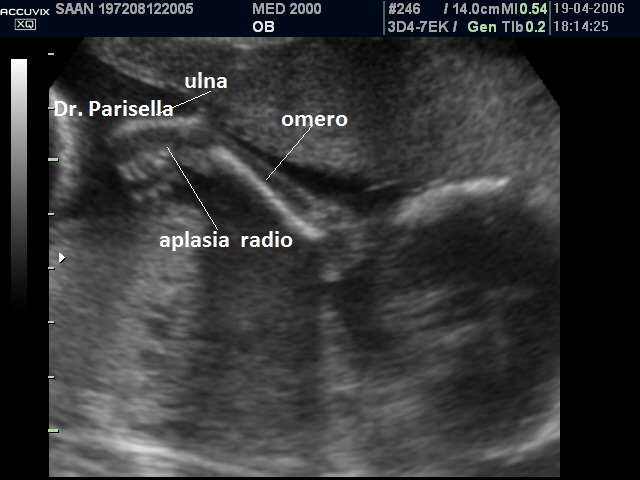

Le anomalie scheletriche più comuni sono le anomalie del raggio radiale: ipoplasia o aplasia del radio, pollice a tre falangi, mano torta, a volte assenza del pollice.

• aplasia/ipoplasia radio